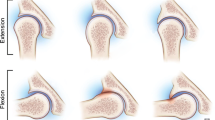

The cam location, anterior or posterior at the femoral head–neck junction (Fig. 1)

All 17 patients with suspected FAI had evidence of an anterior cam deformity on 3D-CT imaging (Fig. 1). There was 100% agreement in terms of presence (19 out of 19) and location (19 out of 19) of the cam deformity when comparing the interpretations made on 3D-MRI with those made on 3D-CT. The simple kappa coefficients for cam presence and locations were both 1. Relative to CT as the reference standard, MRI had an accuracy of 89.5% (17 out of 19) for AIIS characterization, with a simple kappa coefficient of 0.46 between MRI and CT. There were 3 type I and 16 type II AIIS variants on 3D CT imaging (Fig. 2). There were 2 type II variants called on 3D-MRI that were type I on 3D-CT.